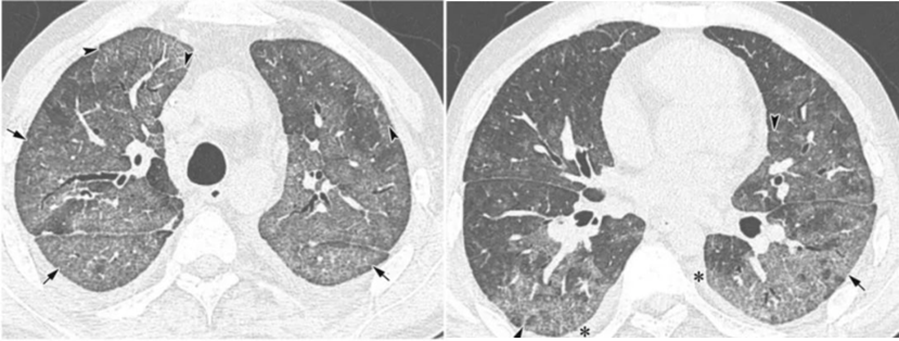

(6)免疫抑制患者的经验性抗CMV指征:①宿主特征:肺移植术后,造血干细胞移植术后。②临床特征:双肺弥漫性磨玻璃影伴小叶间隔增厚。③治疗推荐:更昔洛韦:5 mg/kg q12h。